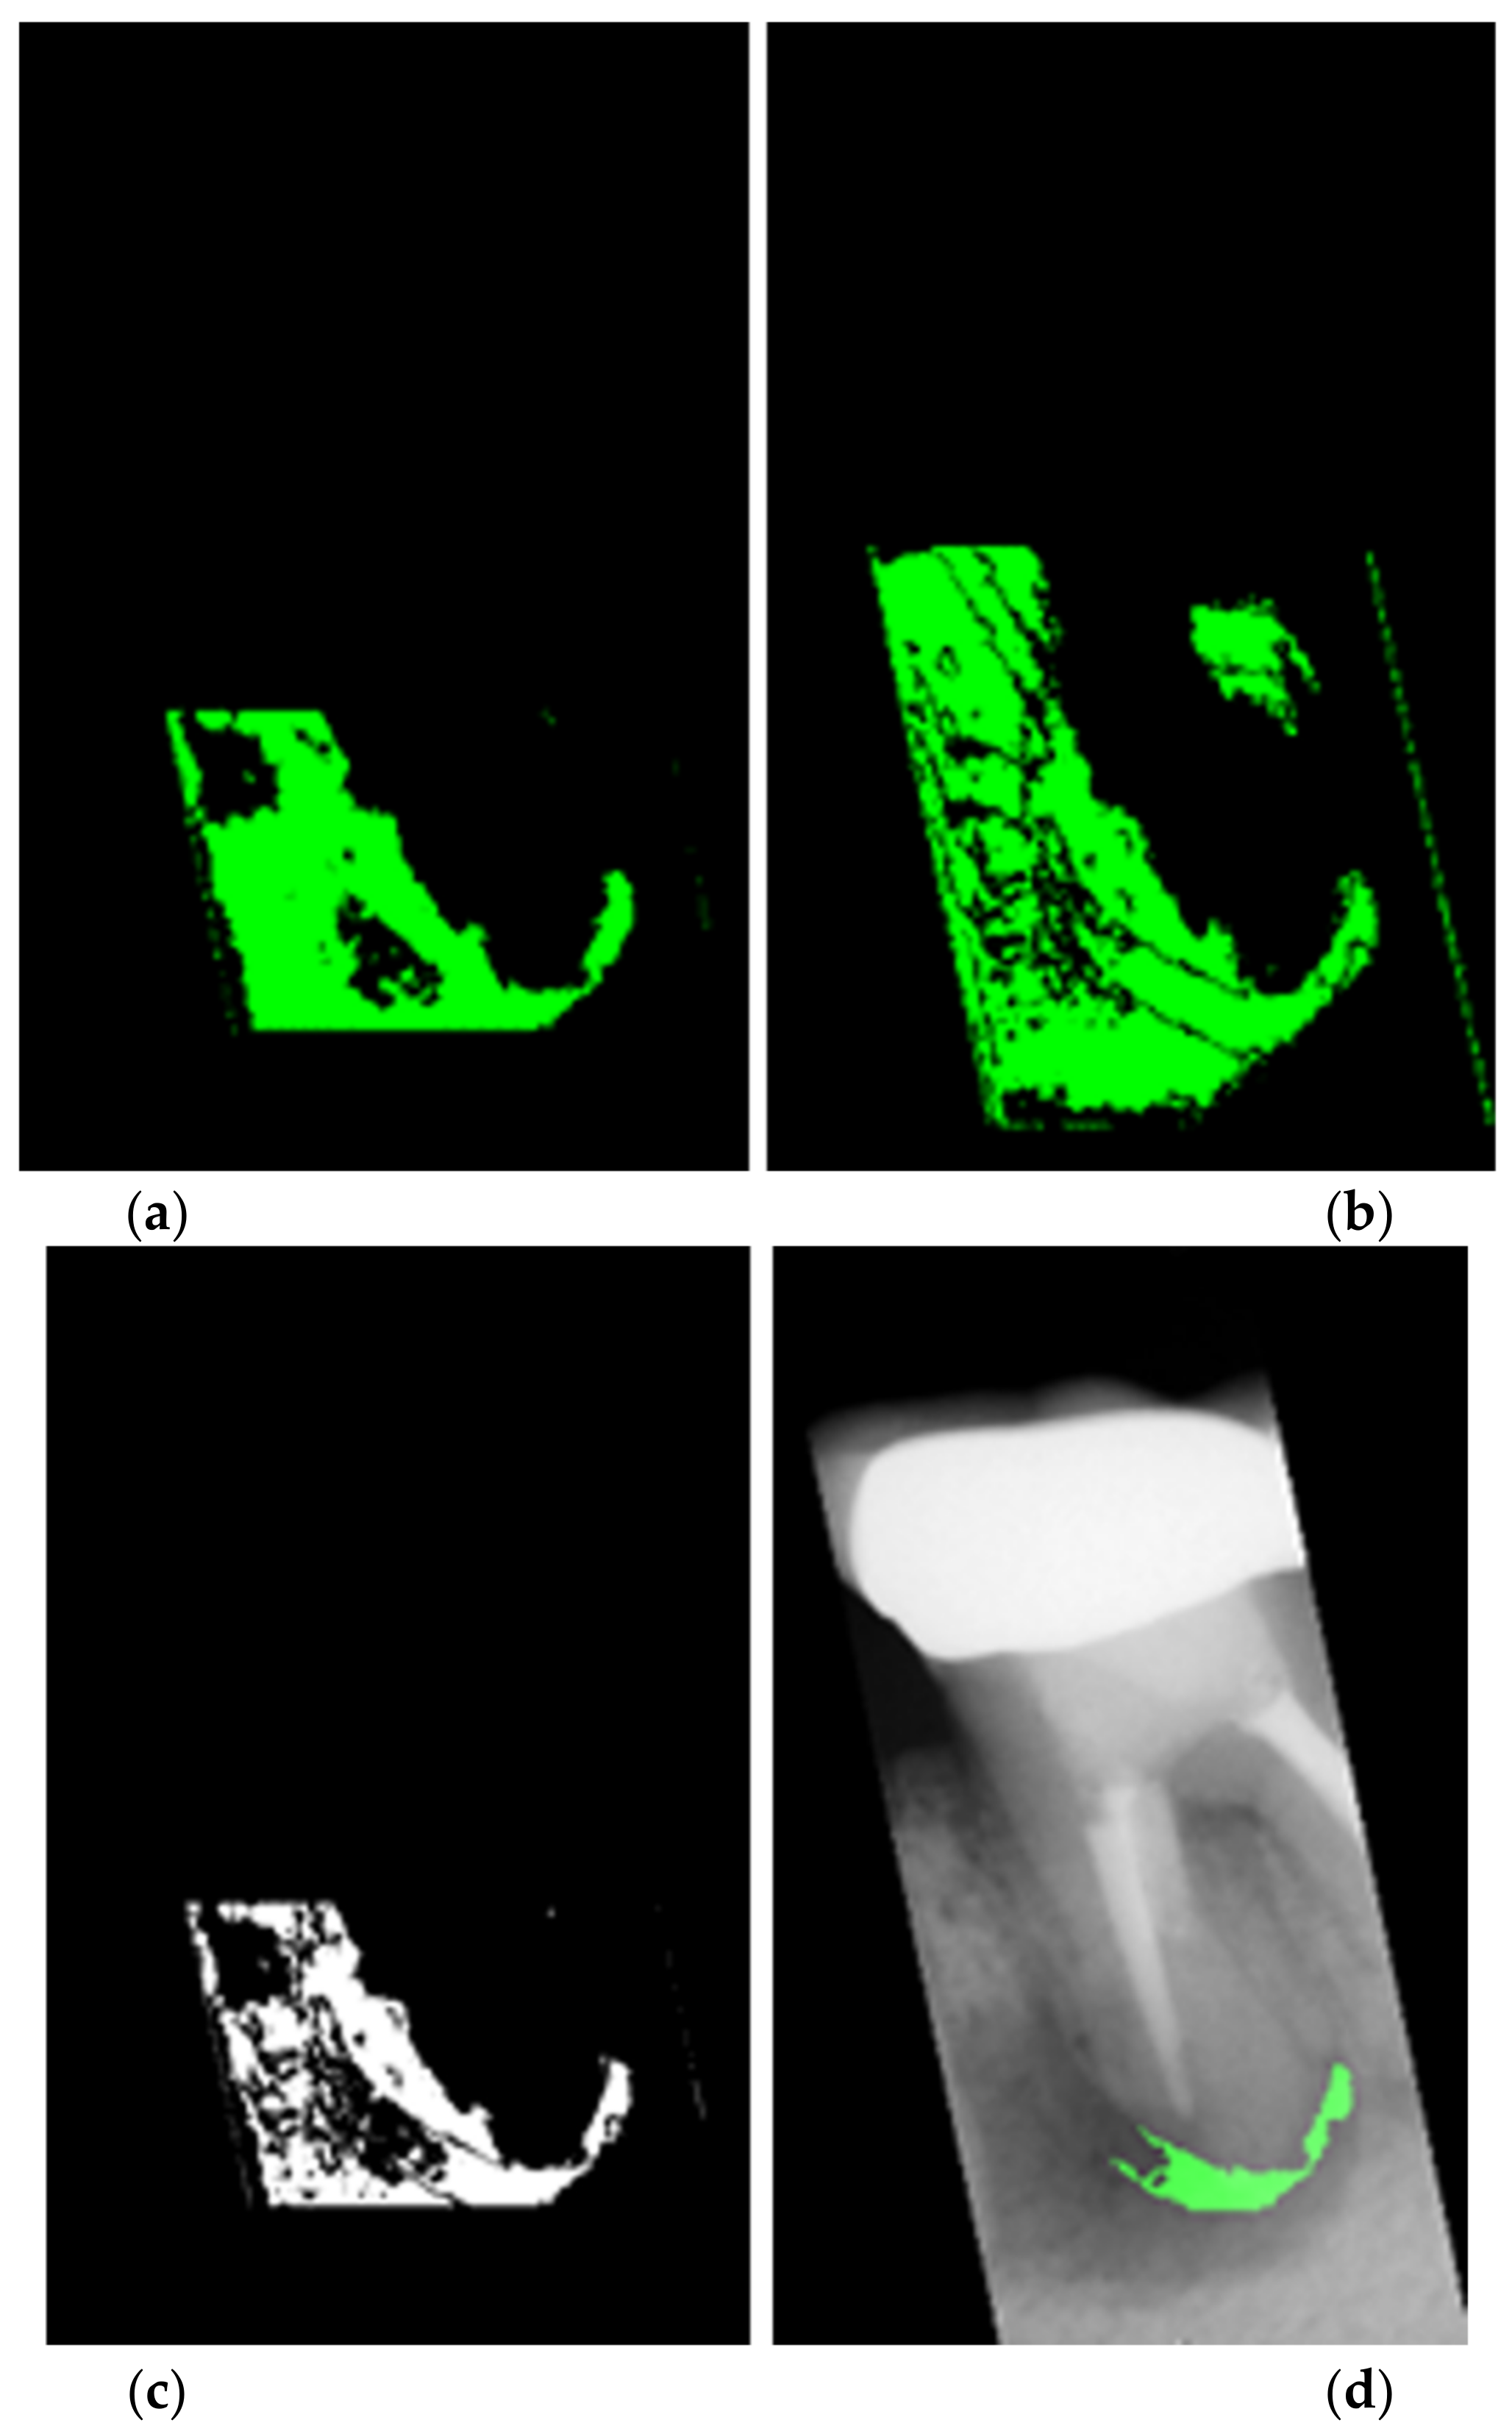

- This study proposes an advanced image enhancement technique for apical lesions. It adds raw grayscale images and Gaussian high-pass filtered images to highlight the possible lesion areas and changes the color of the possible lesion area to green. Experiments show that the accuracy of the model is improved by more than 10% which proves that the proposed method is intuitive and effective.

2.2. Enhancing Lesion

2.2.3. Lesion Heightened